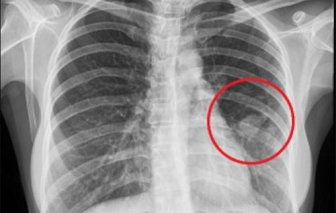

Trong lúc chơi đùa với chị gái, bé trai 13 tháng tuổi bỗng thở gấp gáp, đưa đến bệnh viện bác sĩ phát hiện bị hóc dị vật.